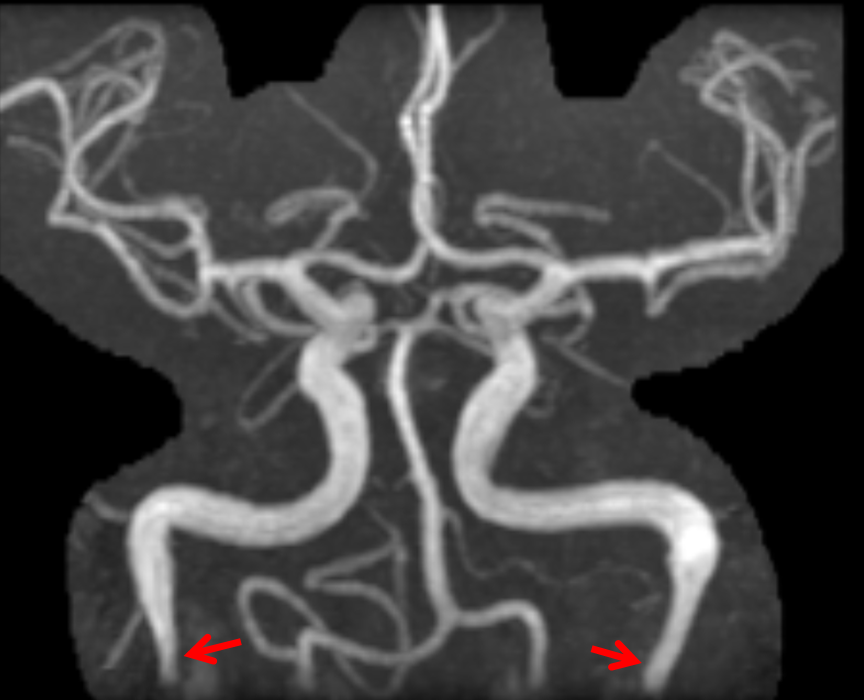

from neuroangio.org

Pulsatile Tinnitus Carotid Artery Dissection

Pulsatile Tinnitus Carotid Artery Dissection Tinnitus Pulsatile It's not usually a sign of anything serious and may get better by. If tinnitus is pulsatile, focus on possible cardiovascular disease or vascular lesions. Pulsatile tinnitus is a rare condition, brought on by constricted blood flow in and around the ears. Perform a head and neck examination, a. Tinnitus is hearing noises that do not come from an outside. Tinnitus Pulsatile.

Pulsatile Tinnitus Carotid Artery Dissection Tinnitus Pulsatile It's not usually a sign of anything serious and may get better by. Pulsatile tinnitus is a rare condition, brought on by constricted blood flow in and around the ears. Pulsatile tinnitus is a type of tinnitus that causes whooshing, thumping, or buzzing sounds in the ears that match the heartbeat. If tinnitus is pulsatile, focus on possible cardiovascular disease. Tinnitus Pulsatile.

Pulsatile Tinnitus Carotid Artery Dissection Tinnitus Pulsatile Pulsatile tinnitus is a rare condition, brought on by constricted blood flow in and around the ears. Pulsatile tinnitus is a rare form of tinnitus that causes a rhythmic swooshing or whooshing noise in your head that matches your heartbeat. It can be caused by various vascular or structural. Pulsatile tinnitus is a type of tinnitus that causes whooshing, thumping,. Tinnitus Pulsatile.

Pulsatile Tinnitus Carotid Artery Dissection Tinnitus Pulsatile If tinnitus is pulsatile, focus on possible cardiovascular disease or vascular lesions. Tinnitus is hearing noises that do not come from an outside source. Pulsatile tinnitus is a rare condition, brought on by constricted blood flow in and around the ears. It's not usually a sign of anything serious and may get better by. Perform a head and neck examination,. Tinnitus Pulsatile.